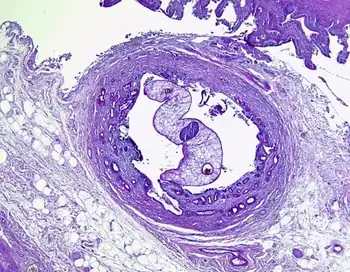

| Opisthorchis sp. in Luschka's duct | |

Opisthorchiasis is a parasitic disease caused by species in the genus Opisthorchis (specifically, Opisthorchis viverrini and Opisthorchis felineus). Chronic infection may lead to cholangiocarcinoma, a malignant cancer of the bile ducts.